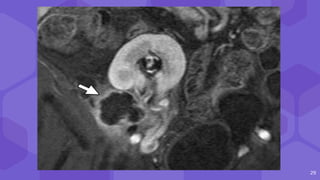

pseudoaneurysm

early draining vein

from the AVF

17